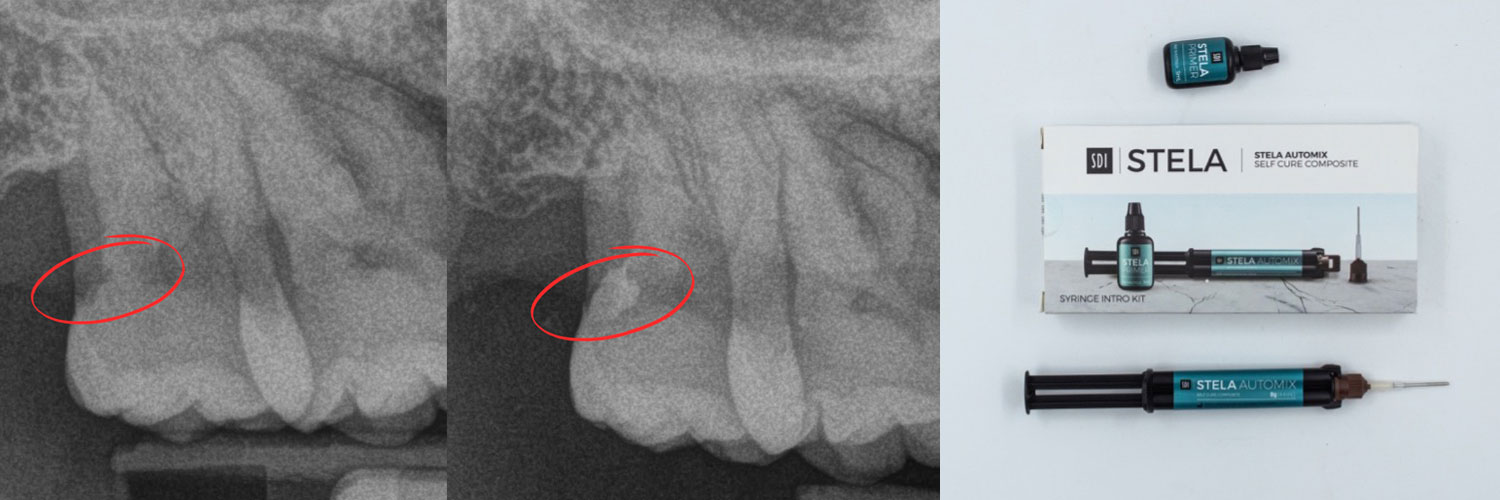

Ho scelto Stela, un materiale progettato per garantire adesione e prestazioni ottimali anche in ambienti umidi. Questa decisione si è rivelata strategica per affrontare le complessità del caso.

- Applicazione di Stela: con l’ausilio del puntale flessibile in dotazione, piegato a circa 30 gradi, il materiale è stato applicato con precisione anche nelle zone più difficili da raggiungere.

- Gestione del restauro: la consistenza ideale di Stela ha consentito una modellazione precisa e senza sbavature. La fase di autopolimerizzazione ha eliminato la necessità di interventi aggiuntivi, garantendo una sigillatura perfetta e una profondità di polimerizzazione illimitata.

Grazie a Stela, il restauro dell’elemento 1.7 è stato completato con successo senza troppe difficoltà. Ecco i punti chiave del risultato:

Ho potuto notare una rapidità di esecuzione, zero gap a livello marginale, estrema lucidabilità e durezza di superficie del restauro ultimato. Stela ha rivoluzionato il mio modo di lavorare!